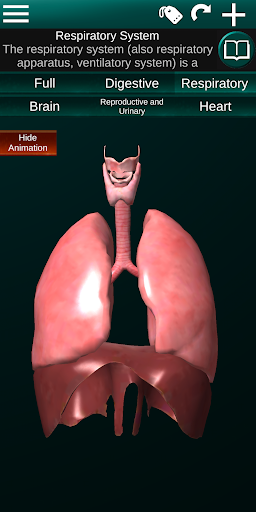

Internal Organs in 3D Anatomy لـ Vodafone Smart N9 Lite

(الأجهزة الداخلية في)

يمكنك هنا تنزيل ملف حزمة تطبيق أندرويد "Internal Organs 3D Anatomy" الخاصة بجهازVodafone Smart N9 Lite مجانًا، نسخة ملف حزمة تطبيق أندرويد - 3.4 للتحميل على Vodafone Smart N9 Lite اضغط ببساطة على هذا الزر. إنه سهل وآمن. نحن نقدم فقط ملفات حزمة تطبيق أندرويد الأصلية. إذا انتهكت أية مواد موجودة في الموقع حقوقك قم بإبلاغنا من خلال